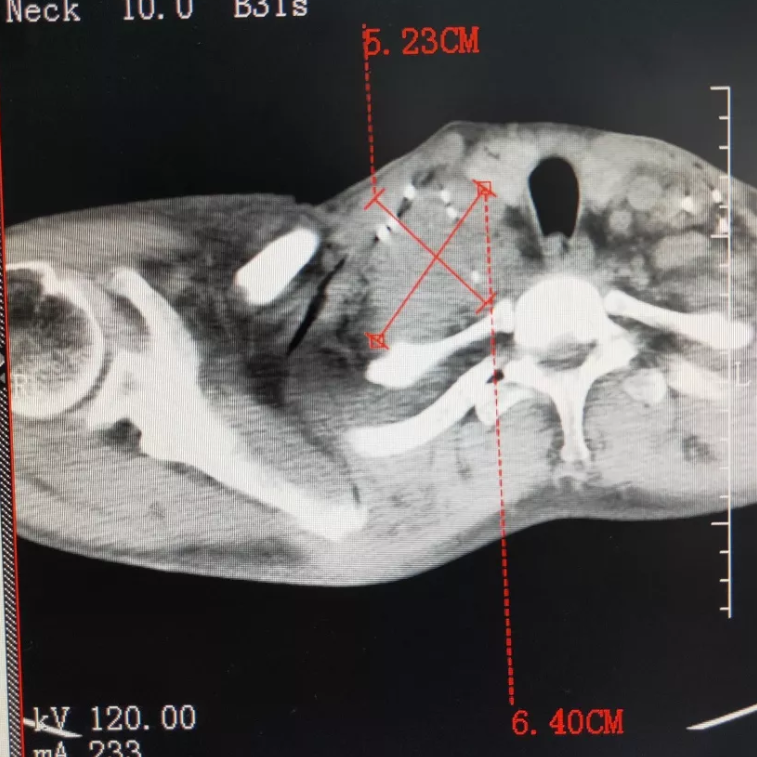

巴基斯坦小伙LEE是一名胸腺癌患者。在当地医院接受常规化疗后,肿瘤不仅未消除,反而越长越大。由于胸腺癌纵隔淋巴结转移,淋巴结肿大压迫食道,导致他的左臂粗胀不堪,严重影响生活。

最终他来到复大医院寻求更好的治疗。考虑到肿瘤恶性程度高,患者手术机会少,对化疗又不敏感,复大专家为其进行了放射性粒子植入结合冷冻消融的局部治疗。术后肿瘤明显缩小,其左臂经过三个月的治疗后也恢复正常。

治疗前

治疗后